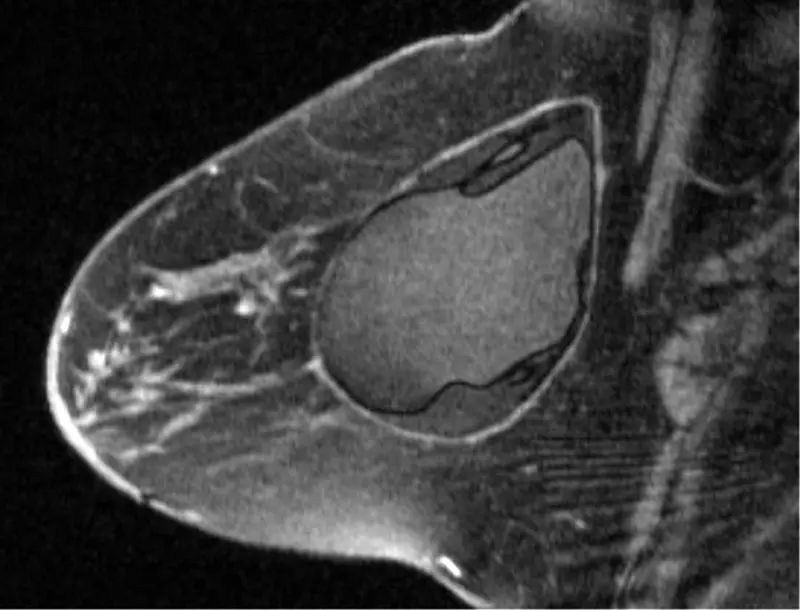

| Capsular Contraction | ![]() Image source [2]: Magnetic resonance imaging (MRI) of a second-generation implant with intra-capsular rupture, there is free silicone liquid within the capsule. Capsular contracture is where scar tissue thickens around the implants, resulting in implant hardening and distortion. |